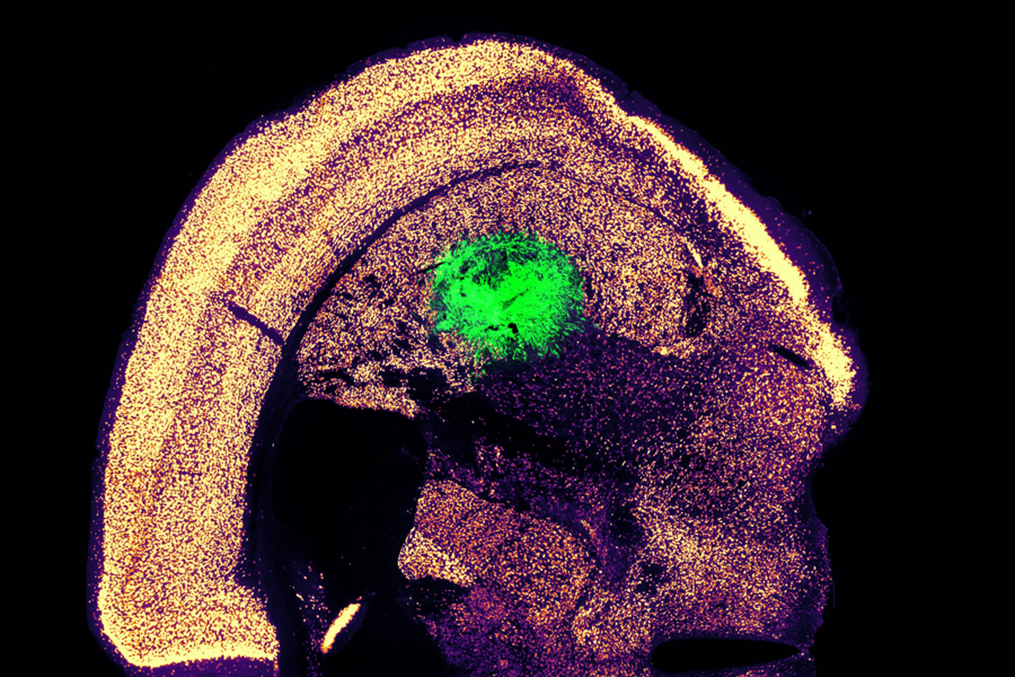

As a first step toward clinicaltranslation, the MIT team demonstrated that their motor neurons could beengrafted into the brains of mice, where they integrated with host tissue.These neurons showed measurable electrical activity and calcium signaling,indicating their ability to communicate with other neurons.